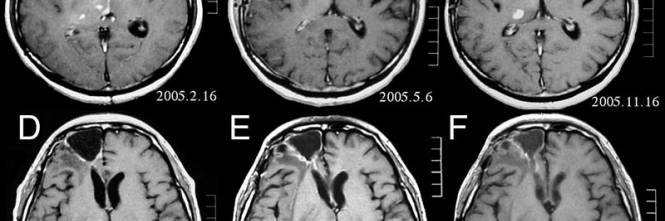

In the California Encephalitis Project from 1998 to 05, 47 (3%) of 1570 cases of encephalitis presented with the rapid evolution to fulminant cerebral edema, and 34 (723%) patients died within 7 days after hospitalization 17 In our study, 25 (24%) of 1038 children with encephalitis presented with fulminant cerebral edema, 16 (64%) of whom. Si bien no presentó lesiones cutáneas inicialmente, la vasculopatía cerebral, en ausencia de dicho antecedente, ocurre en un 40% de los casos 1,3 A pesar del tratamiento instaurado, la paciente presentó una mala evolución debido a una complicación extremadamente rara en este contexto el edema cerebral difuso. Edema vasogenico, ovvero associato ad alterazione della permeabilità dei capillari, che aggiunge liquidi al tessuto cerebrale, aumentandone la diffusività Un caso tipico è l’edema perilesionale di masse neoplastiche Patologie degenerative (es Alzheimer), in cui si verifica perdita di sostanza, bianco e/o grigia, con aumento della.

Edema vasogenico, ovvero associato ad alterazione della permeabilità dei capillari, che aggiunge liquidi al tessuto cerebrale, aumentandone la diffusività Un caso tipico è l’edema perilesionale di masse neoplastiche Patologie degenerative (es Alzheimer), in cui si verifica perdita di sostanza, bianco e/o grigia, con aumento della. Un edema cerebrale reversibile è riscontrato nell’8% delle SVCR Esso è di insorgenza precoce, spesso nei primi giorni della SVCR, sotto forma di ipersegnali bilaterali e simmetrici in sequenza RM FLAIR, paragonabili a quelli descritti nella sindrome di encefalopatia posteriore reversibile. Cerebral edema simply means swelling of the brain Cerebral edema is a relatively common phenomenon with numerous causes Cerebral edema can be asymptomatic, merely seen on imaging, or it can cause lifethreatening complications 1) Cerebral edema is categorized into either vasogenic, cellular, osmotic, and interstitial causes 2).